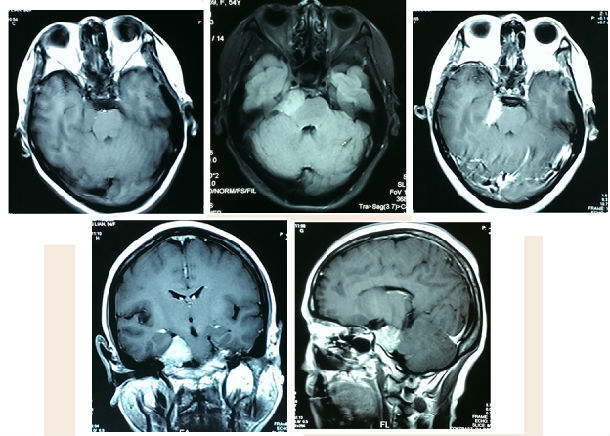

斜坡巨大脑膜瘤一例切除

图片尺寸1226x929